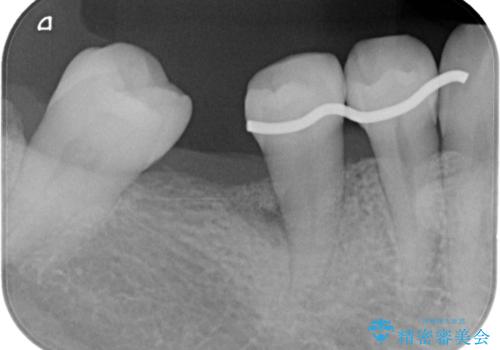

右下小臼歯は歯周病で大きな骨欠損を認めていました。

歯周病の原因に咬合干渉が疑われる為、ワイヤーにて固定を行っています。